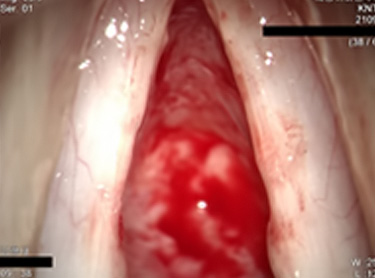

수술 전 성대